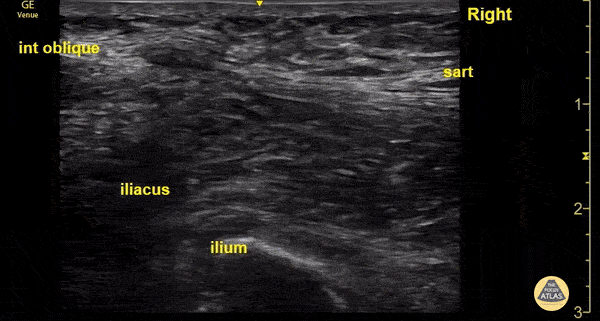

An 89 year old male presented after a mechanical fall onto his right hip. X-rays demonstrated a comminuted right intertrochanteric fracture. An ultrasound-guided fascia iliaca block can be performed using the suprainguinal approach when placing the probe perpendicular to the inguinal ligament. The internal oblique (cephalad, blue) and the sartorius (caudad, red) muscles are encompassed by the fascia lata (green) superiorly and the fascia iliaca (yellow) inferiorly. These two come together to form a “bow tie” as shown above, anesthetic is deposited below the fascia iliaca. Studies have shown improved analgesia with the suprainguinal, as it is believed to have a higher likelihood of blocking the lateral femoral cutaneous nerve and the obturator nerve. Sanna Ho-Gotshall, DO, Ultrasound Fellow Casey Wilson, MD, Ultrasound Director, Emergency Medicine Program Director